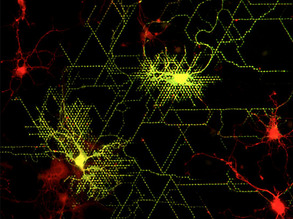

Painting by Neurons